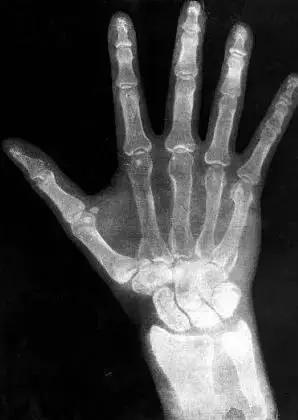

3.X光:屏幕上意外看到自己手掌骨骼 惊呆物理学家

1895年的一天,德国物理学家威廉·伦琴在德国维尔茨堡大学的实验室中忙碌地研究阴极射线管的特性时,突然注意到一束光投射到了屋内另一头的氰亚铂酸钡荧光纸板屏幕上,接着他发现纸板屏幕上出现了一只形同骷髅的手掌骨骼,他最初的惊讶顿时变成了震惊。

伦琴很快意识到,一些神秘的辐射光不但穿过了空气、并且穿过了他的血肉,从而使他的手掌骨骼投影在了光线暗淡的纸板屏幕上。这种光的粒子显然能够穿过固态物体,伦琴接着发现,他可以借助这种超乎想像的辐射光来产生清晰的体内图像。就这样,世界上第一幅X光片诞生了。X光之所以叫X,是因为X是未知事物的代称。没多久,世界各地的科学实验室都开始复制出X光机,20年后,X光开始大量用于医学目的。由于X光是大自然的一种现象,所以准确地说,伦琴是意外发现了X光,而不是发明了X光。